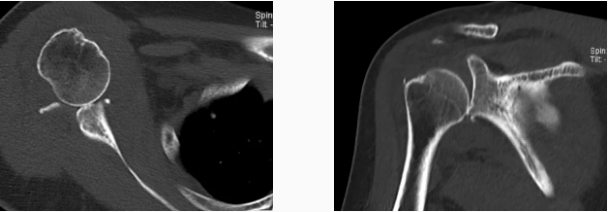

病例2

病史摘要:女性,65歲,跌傷致右肩活動(dòng)受限9天。

MR圖示:右側(cè)肱骨頭后上部局部明顯凹陷,骨皮質(zhì)欠光整,周圍見片狀壓脂高信號(hào)影(箭頭);前盂唇脫離移位;前下盂唇不連,局部骨質(zhì)分離(三角形);肱骨頭向前移位。